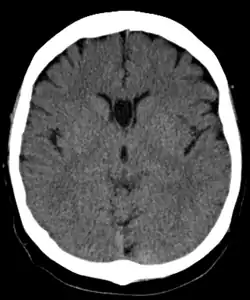

Cave of septum pellucidum seen on CT

The cave of septum pellucidum (CSP), cavum septi pellucidi, or cavity of septum pellucidum is a slit-like space in the septum pellucidum that is present in fetuses but usually fuses during infancy. The septum pellucidum is a thin, laminated translucent vertical membrane in the midline of the brain separating the anterior horns of the right and left lateral ventricles. It lies posterior to the corpus callosum. Persistence of the cave of septum pellucidum after infancy has been loosely associated with neural maldevelopment and several mental disorders that correlate with decreased brain tissue.[1][2][3][4][5]

There are individual differences in the degree of CSP; whereas some have complete closure of the cavum, others present with a small degree (4–6 mm wide, in the coronal plane) of incomplete closure.[4] The most common type of CSP is noncommunicating; that is, it does not connect to the brain's ventricular system. Because of this lack of communication, the previous use of the term "fifth ventricle" is no longer used, and the fifth ventricle is the name often used for the terminal ventricle.